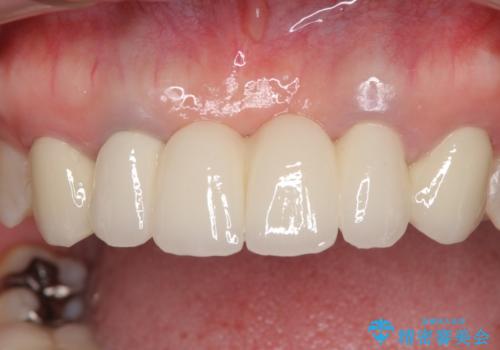

金属を使用した前歯のブリッジや奥歯の銀歯は全てオールセラミッククラウンまたはセラミックインレーとし、左下の奥歯はインプラントにより治療を行うこととしました。

矯正治療までは考えていなかったそうですが、物が挟まっていた前歯のスペースがなくなり、矯正治療を行って良かったとのことでした。